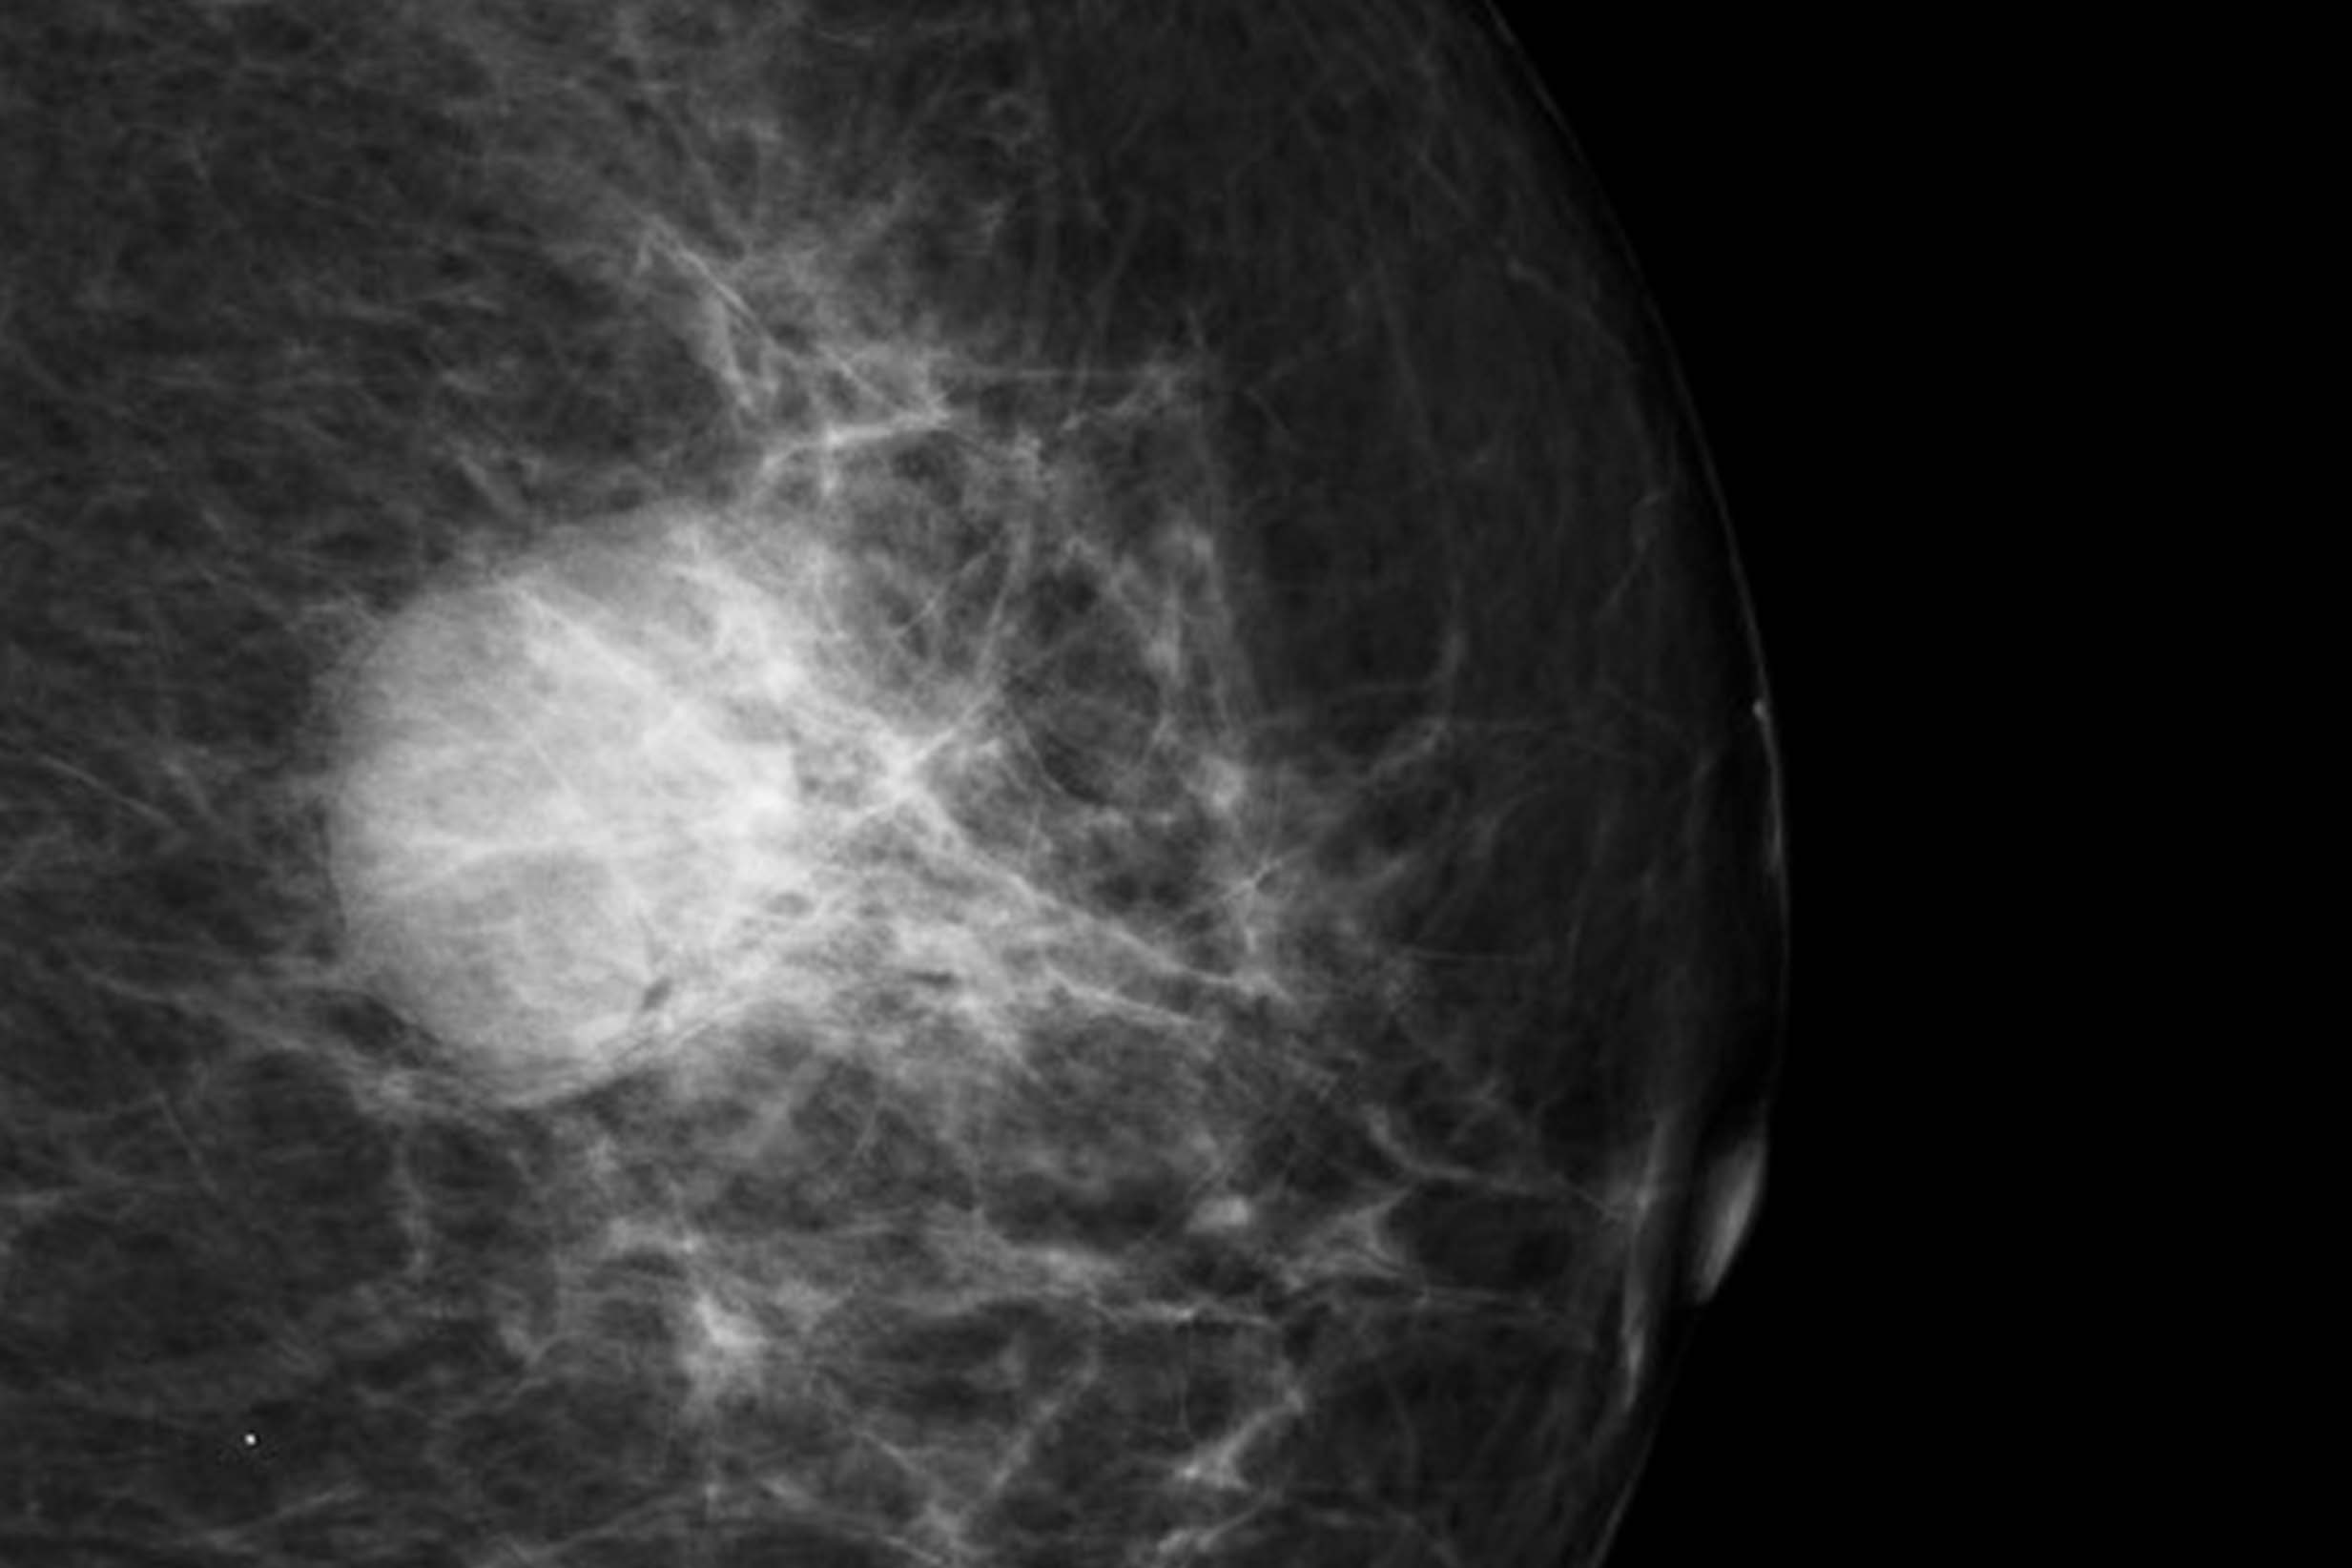

An image of a breast tumor (invasive ductal carcinoma) on a mammogram.

Courtesy of Heba Khaled Al Ja’afreh, Radiopaedia.org.

Lumps or masses

There are many types of lumps or masses, like fibroadenomas and cysts, that can be seen on a mammogram. If a mass is at least partly solid, more tests (especially an ultrasound test) may be needed to check if it could be cancerous.